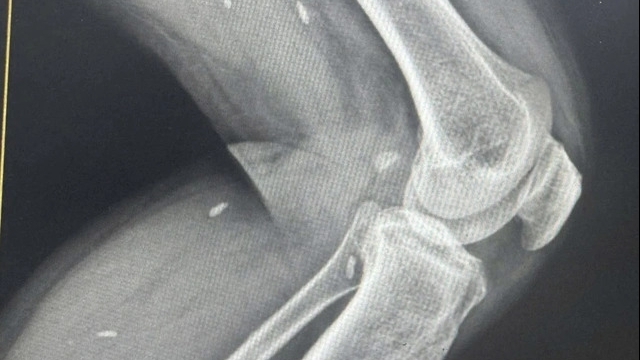

| Cấp cứu cho bệnh nhân Sao tại Bệnh viện Hữu nghị Việt Đức, ngày 29/1. Ảnh: V.T |